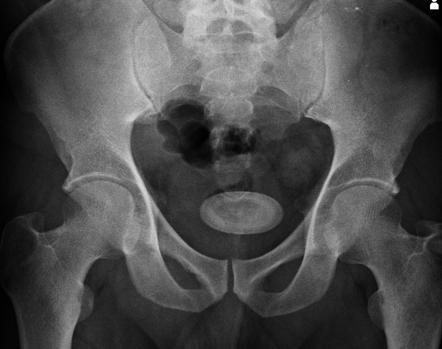

Vesikolitiasis adalah massa keras yang memiliki bentuk seperti batu dan terletak di saluran kemih manusia. Massa keras seperti batu tersebut juga bisa terbentuk dalam ginjal dan disebut dengan batu ginjal atau nefrolitiasis. Vesikolitiasis terjadi ketika ada massa keras seperti batu yang menghalangi aliran urine.

Penyakit ini disebut juga dengan batu kandung kemih karena ditandai dengan munculnya massa keras yang mirip seperti batu dalam kandung kemih. Batu tersebut terbentuk dari endapan mineral dalam kandung kemih. Ukuran batu kandung kemih sendiri cukup beragam dan berbeda-beda antara satu penderita dengan penderita yang lain.